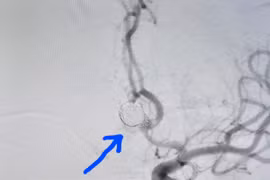

Phình mạch máu não – “Sát thủ thầm lặng” không thể coi thường

Nhiều nghiên cứu cho thấy tỉ lệ tồn tại phình mạch não có thể tới 5% dân số. Mỗi năm có khoảng 50000 người Mỹ bị đột quỵ do vỡ phình mạch não, 2/3 trong số đó chết hoặc để lại di chứng hết sức nặng nề.